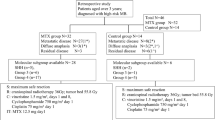

Eligible patients included children ≤21 years of age with medulloblastoma, ependymoma, or atypical teratoid/rhabdoid tumor (ATRT) that originated in the posterior fossa and subsequently recurred anywhere in the brain and/or spine. Patients were excluded if they were pregnant, receiving any other chemotherapy, or enrolled in another experimental protocol. An estimated life expectancy of at least 12 weeks and a Karnofsky or Lansky performance score of 50 or greater was required [2].

Seven patients with a median age of 12 years (range 4–19 years) were enrolled (Table 2). Five patients had recurrent medulloblastoma, and two had recurrent anaplastic ependymoma. All seven patients had progressive disease at the time of enrollment despite prior surgery, radiation therapy, and various chemotherapy regimens. Two patients (patients 1 and 3) had received prior intravenous methotrexate, both at least 3 years prior to enrollment.

All patients underwent successful surgical implantation of the catheter and VAD. Simultaneously, three patients underwent subtotal resection of tumor located in the fourth ventricle or cerebellum, and one patient underwent simultaneous tumor biopsy. The remaining three patients did not have disease in the posterior fossa amenable to simultaneous resection. Six patients had no new neurological deficits after surgery, and one patient (patient 7) had partial left-sided facial weakness postoperatively. This patient had undergone simultaneous subtotal resection of tumor (ependymoma) that was filling the fourth ventricle. The post-operative seventh nerve palsy was attributed to resection of tumor close to the floor of the fourth ventricle and did not resolve for the duration of follow-up. Post-operative MRI scans in all patients demonstrated catheter placement in the fourth ventricle without injury to the brainstem or cerebellum (Fig. 2). In all patients, CINE MRI sequences confirmed CSF flow from the fourth ventricular outlets to the cervical, thoracic, and lumbar spinal subarachnoid spaces. Nuclear medicine CSF flow studies were therefore not required in any patients.

Two patients (patients 3 and 6) underwent surgery for VAD implantation but never received methotrexate infusions. Both of these patients were discharged from the hospital postoperatively with no new neurological deficits. In the interval between surgery and the planned first cycle, both patients had rapid disease progression. Patient 3 presented with irritability and decreased strength in his arms and legs 2 weeks postoperatively. A new MRI scan demonstrated massive hydrocephalus caused by widespread worsening of leptomeningeal tumor throughout the brain as well as tumor progression in the spine causing spinal cord compression. A palliative ventriculoperitoneal shunt was placed, and he was taken off study without ever receiving methotrexate infusions. He died 10 days later. Similarly, patient 6 presented 7 days postoperatively with swallowing difficulty and facial asymmetry followed by vomiting and lethargy. An MRI demonstrated massive tumor progression throughout the brain. She was taken off study and died 2 days later.